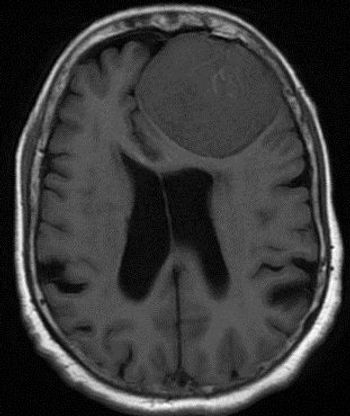

35-year-old female with prior history of breast carcinoma presented with frontal headaches.